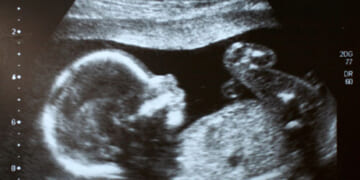

This week, JAMA Network Open published a study that analyzed the impact of recently enacted pro-life laws on maternal mortality rates. Overall, the results should please pro-lifers. The study found that maternal mortality rates are falling in…